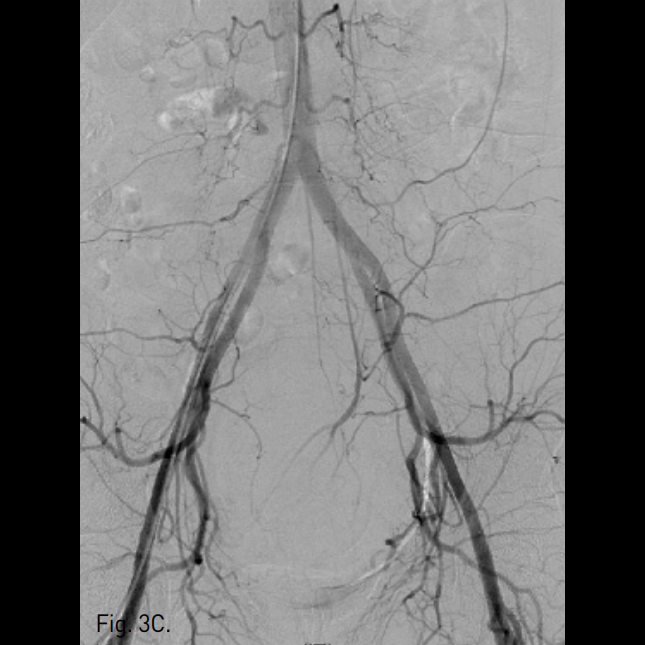

Fig. 1

Transvaginal ultrasonogram reveals a huge myoma, measuring 5.5 × 5.1cm in size.